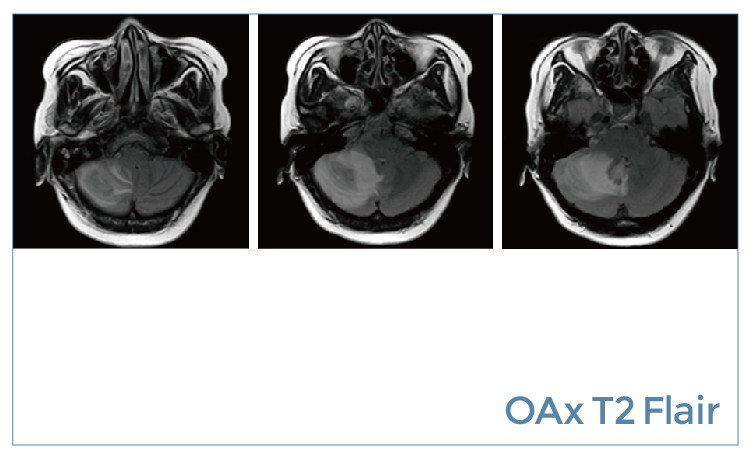

【朗润影像档案】磁共振影像病例分享(编号20190802)